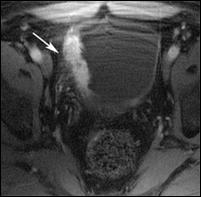

4.4. Rezonanta magnetica nucleara ofera cateva avantaje comparativ cu tomografia computerizata: tesutul tumoral este diferentiat mai bine de peretele vezical normal; examinarea se poate efectua in mai multe planuri; ganglionii limfatici se individualizeaza mai bine, putand fi deosebiti de vasele sanguine, si nu este necesara administrarea i.v. de substanta de contrast. In acelasi timp insa, miscarile pacientului pot induce artefacte neinterpretabile pe film, iar pacientii cu stimulatoare cardiace, clipuri vasculare metalice sau alte proteze metalice reprezinta contraindicatii pentru examenul prin RMN.

Cu toate progresele investigationale imagistice moderne, nici o tehnica de examen nu poate diferentia cu certitudine tumorile Ta de T1 sau T2 de T3a. Cel mai mare beneficiu diagnostic al tomografiei computerizate si al rezonantei magnetice nucleare consta in diferentierea corecta a tumorilor infiltrative, dar inca intra-organ (pana la T3a) de cele cu extensie extravezicale (T3b - T4a sau b). In privinta adenopatiei regionale, prin ambele metode se apreciaza ca ganglionii cu diametre mai mari de 1 cm sunt practic totdeauna invadati tumoral, in timp ce adenopatiile cu diametre mai mici considerate reactive, desi in cadrul acestora unele sunt totusi determinari neoplazice.

Figura 43. a,b,c,d) Imagini RMN de tumora vezicala.